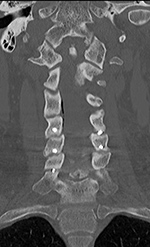

| 68 year-old woman with posterior spinal fixation extending from the occiput to C3 involving posterior elements of C2 and C3 (left image). The surgery was performed for unstable atlantoaxial subluxation after remote cervical spine trauma. CT imaging follow-up (right image) demonstrated the C2 and C3 fixation screws were posteriorly displaced into the spinal musculature. |